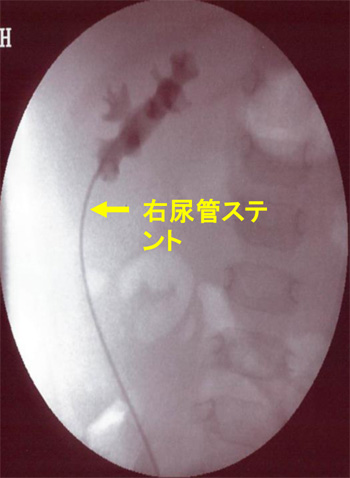

手術の準備

・手術に先立ち膀胱鏡を用いて

・手術に先立ち膀胱鏡を用いて

両側尿管ステント留置

偏位の強い尿管の位置を確認